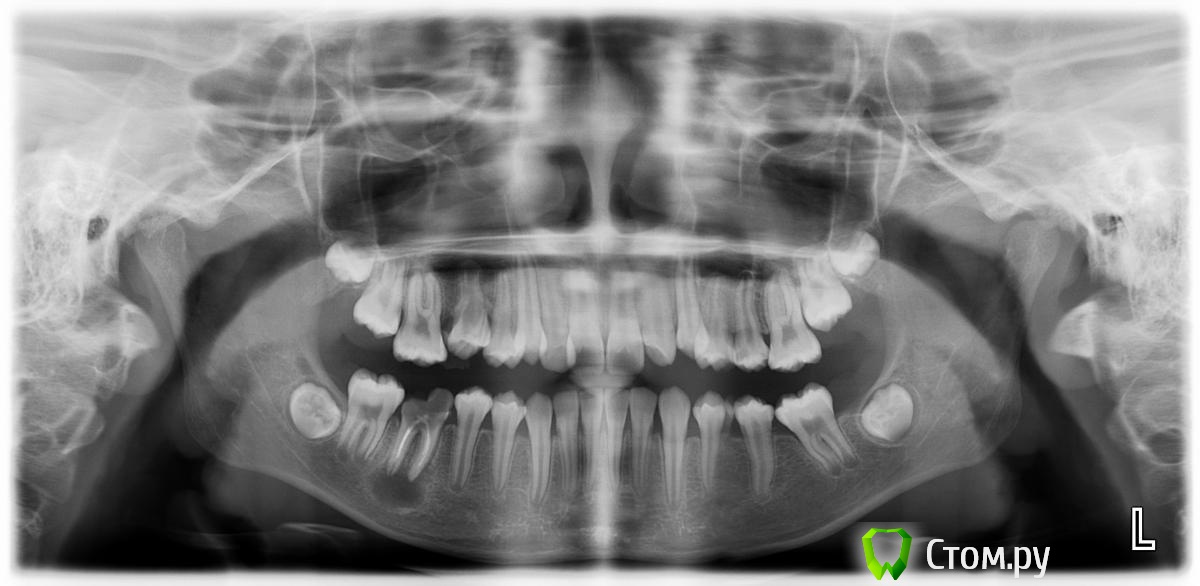

zzkz Опубликовано 25 октября, 2014 Поделиться Опубликовано 25 октября, 2014 Девочке 12 лет. Удалил ей зуб 46. Все откюретажил. Какова дальнейшая тактика ведения? Ссылка на комментарий

red_butler Опубликовано 25 октября, 2014 Поделиться Опубликовано 25 октября, 2014 (изменено) Какова дальнейшая тактика ведения?консультация ортодонта3.6 родители, тоже проглядели? Изменено 25 октября, 2014 пользователем red_butler 1 Ссылка на комментарий

Bier Опубликовано 25 октября, 2014 Поделиться Опубликовано 25 октября, 2014 К ортодонту надо, уже 16 опустился 1 Ссылка на комментарий

zzkz Опубликовано 25 октября, 2014 Автор Поделиться Опубликовано 25 октября, 2014 Ортодонт в плане конечно есть. С моей стороны все на этом?Можем ли ждать в будущем асимметрии, микрогнатии и т.п.?Хотелось бы услышать еще и мнения ортодонтов, для себя(надеюсь заглянут). Своему ортодонту доверяю, но 2 головы как говорится лучше.. Ссылка на комментарий